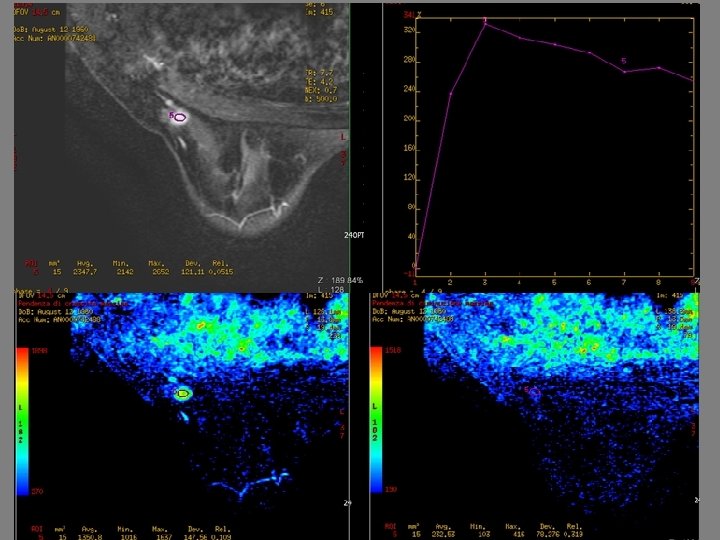

RM e MAMMELLA DENSA • Acquisizione immagini RM prima e dopo somministrazione di mdc ev paramagnetico • Rielaborazione e ricostruzione delle immagini ( sottrazione e MIP) • Curve intensità tempo( ROI) • Mappe a colori (rosso, verde, giallo) basate sulla pendenza di crescita massima e sulla pendenza di diminuzione massima MIGLIORE CAPACITA’ DISCRIMINATIVA TRA POTENZIAMENTI PATOLOGICI E POTENZIAMENTI FISIOLOGICI DOVUTI ALL’ELEVATA DENSITA’ MAMMARIA. COMBINAZIONE DI ELEVATA RISOLUZIONE TEMPORALE E BUONA RISOLUZIONE SPAZIALE. MAGGIORE ACCURATEZZA DIAGNOSTICA